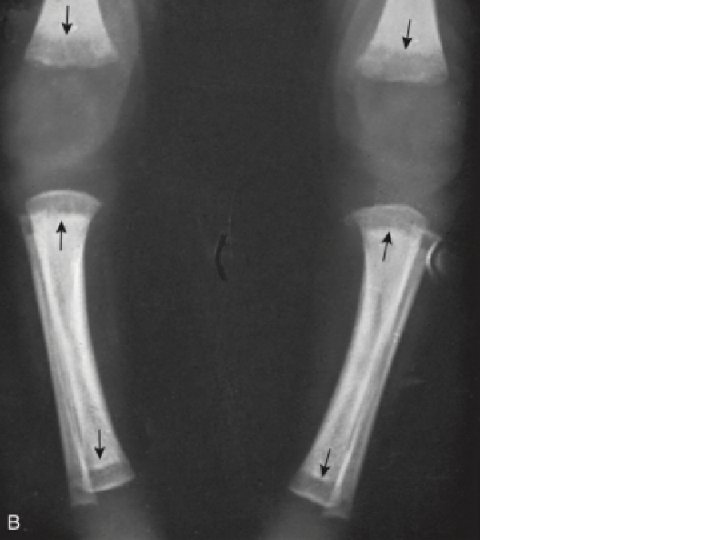

Sinal de Wimberger Destruição medial da metáfise proximal da tíbia

Pseudoparalisia de Parrot sífilis congênita precoce

Sinal de Wimberger: lesão na metáfise medial da tibia. sífilis congênita precoce

SC: Acometimento múltiplo de ossos, principalmente nas diáfises e metáfises